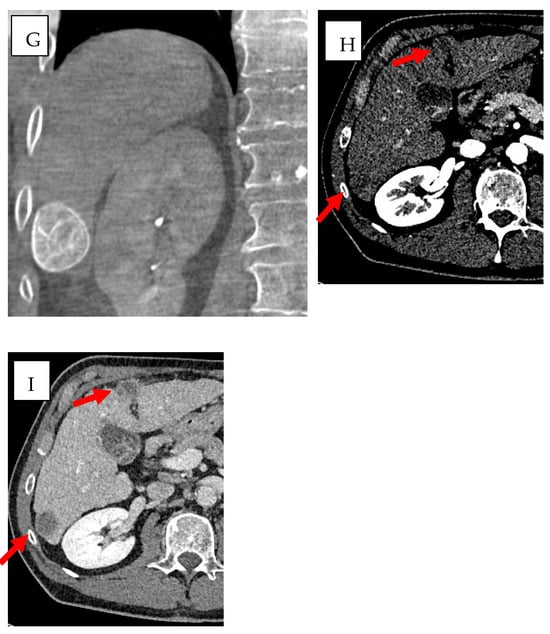

In vascular procedures, CBCT can be used in addition to automated tumor feeder detection [] to improve both safety and precision of embolization therapies. The AFD systems, achieving real-time 3D visualization of blood vessels through advanced imaging techniques with intelligent algorithms [,], consisting in three steps, in which the first step is the manual identification and segmentation of a ROI, the second is the manual identification of tip of catheter, and finally the last step is the automated identification of feeding arteries. The final 3D roadmap, containing the segmented ROI and feeding arteries and the paths from catheter to vessels, has been overlaid onto the live fluoroscopy images [] (Figure 2).

Figure 2.

Multifocal HCC in a patient with HBV/HDV/alcohol-related cirrhosis (BCLC stage B) treated with DEB-TACE using BioPearl (Tokyo, Japan). (A,B) Pre-treatment CT shows two subcapsular lesions (~3 cm) in segments VI and IV with (A) arterial hyperenhancement and (B) venous washout (red circles), consistent with HCC. (C,D) Emboguide (Version 1.2.1, Philips) software and CBCT mapping of the arterial pathway from the right hepatic artery to the target lesion in segment IV. (E) Angiographic image showing the lesion in segment IV supplied by the left hepatic artery. (F,G) Emboguide (Philips) software and CBCT mapping of the right hepatic artery pathway to the lesion in segment VI before chemoembolization, showing enhancement of the target area. (H,I) Post-treatment CT in (H) arterial and (I) venous phases demonstrates hypodense areas (~3.5 cm) in segments VI and IV, consistent with treated lesions (red arrows).

These software utilize dynamic contrast-enhanced imaging for peak vessel visualization which enhances vascular structure definition, especially when dealing with tumors displaying irregular or abnormal blood supply. Real-time integration of these images enables precise catheter navigation which supports embolization procedures with reduced requirements for extensive fluoroscopy exposure [,].